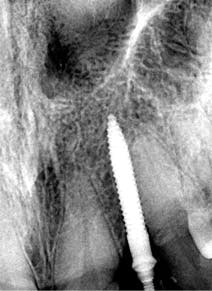

Figure 9: Implant placement

Figure 10: Implant exposed for impression

A 1.8 mm x 14 mm Anew implant (Dentatus) was selected, and a surgical guide was fabricated for a flapless approach. In this instance, a healing cap was placed, and the existing flipper was relieved to address financial concerns (figures 9 and 10). A screw-retained crown was fabricated three months post insertion (figures 11 and 12). The patient reported no postoperative discomfort, and the case remains successful, as shown in the two-year postoperative x-ray (figure 13).